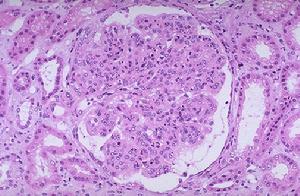

3.腎組織電鏡病理檢查見GBM廣泛變厚破裂,並與變薄的GBM並存。

4.抗膠原ⅣNC1抗體作免疫螢光檢查,表皮基底膜及GBM均不著色(男性)或僅節段淺染(女性)。

遺傳性腎炎1.家族性良性薄基底膜病(家族性良性血尿) 家族性良性薄基底膜病為常染色體顯性遺傳。臨床特點為反覆發作肉眼血尿,非進行性疾病,預後良好,不發生腎功能衰竭,無耳、眼疾患。腎活檢光鏡下正常,免疫螢光陰性電鏡下GBM瀰漫變薄

儘管瀰漫性基底膜變薄被認為是良性家族性血尿的標誌,但有一些瀰漫性基底膜變薄的患者是有進行性腎功能衰竭家族史的。瀰漫性腎小球基底膜變薄可能是一種奧爾波特綜合徵的頓挫型或是腎小球基底膜改變的早期階段。患奧爾波特綜合徵的幼年兒童和成年女性常常表現為基底膜變薄,而年老的患者往往表現為明顯的基底膜增厚和花籃狀。Rumpelt發現腎小球基底膜在男性患者隨著年齡的增加而花籃狀程度加深,而在女性患者則仍保持薄基底膜狀態換言之,腎小球基底膜變薄不一定預示是良性的薄基底膜病,僅僅發現腎小球基底膜變薄可能會引致錯誤的臨床病理結論。因此,當在腎活檢標本發現緻密層變薄時,仔細詢問患者家族史,繼而檢查有無蛋白尿、聽力障礙眼科學異常,以鑑別奧爾波特綜合徵和薄基底膜病。但感覺神經性耳聾對奧爾特綜合徵的診斷並非必需。

6.其他有基底膜緻密層改變的疾病 近期研究對本病腎小球基底膜改變的特異性提出質疑。在兩大組非選擇性的腎活檢標本中6%~15%的標本可見局灶性層狀和分離的緻密層,主要發生在感染後腎小球腎炎、局灶性節段性腎小球硬化和透明變性、IgA腎病和與表現為腎病綜合徵的系膜增生性腎小球腎炎因此當考慮奧爾波特綜合徵診斷時,應臨床聯繫,並對腎組織進行免疫螢光顯微鏡檢查瀰漫性腎小球基底膜增厚和分離現象是診斷奧爾波特綜合徵重要依據。如發現IgM、C3、備解素C4等在內皮下沉積,則考慮IgM腎病膜增殖性腎小球腎炎和其他免疫複合物介導的腎小球腎炎。